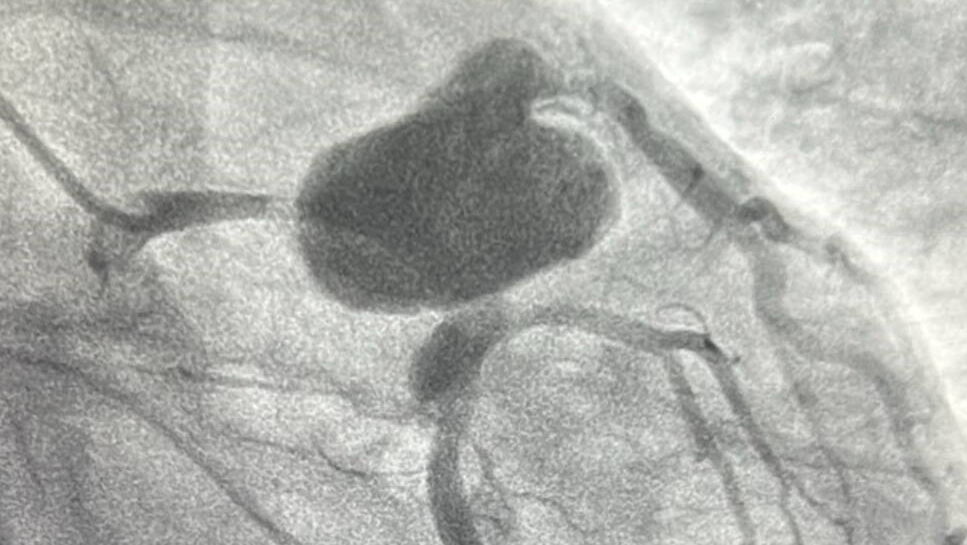

Por otro lado, se trató la exclusión del aneurisma mediante un stent cubierto (graft) de alta especialización, sellando la dilatación gigante que afectaba al tronco de la coronaria izquierda y a sus principales ramas: descendente anterior, bisectriz (ramus) y circunfleja. Tras la operación, el paciente ha evolucionado favorablemente y ya se encuentra en su domicilio.

Un aneurisma coronario es una “bolsa” o dilatación que se forma en una arteria del corazón. Aunque las coronarias miden solo unos milímetros de diámetro, en este caso la dilatación alcanzó casi 10 centímetros.

Un aneurisma tan grande puede presionar estructuras vecinas y dificultar el paso de la sangre, causando dolor en el pecho, arritmias o incluso complicaciones graves si se rompe o se trombosa.